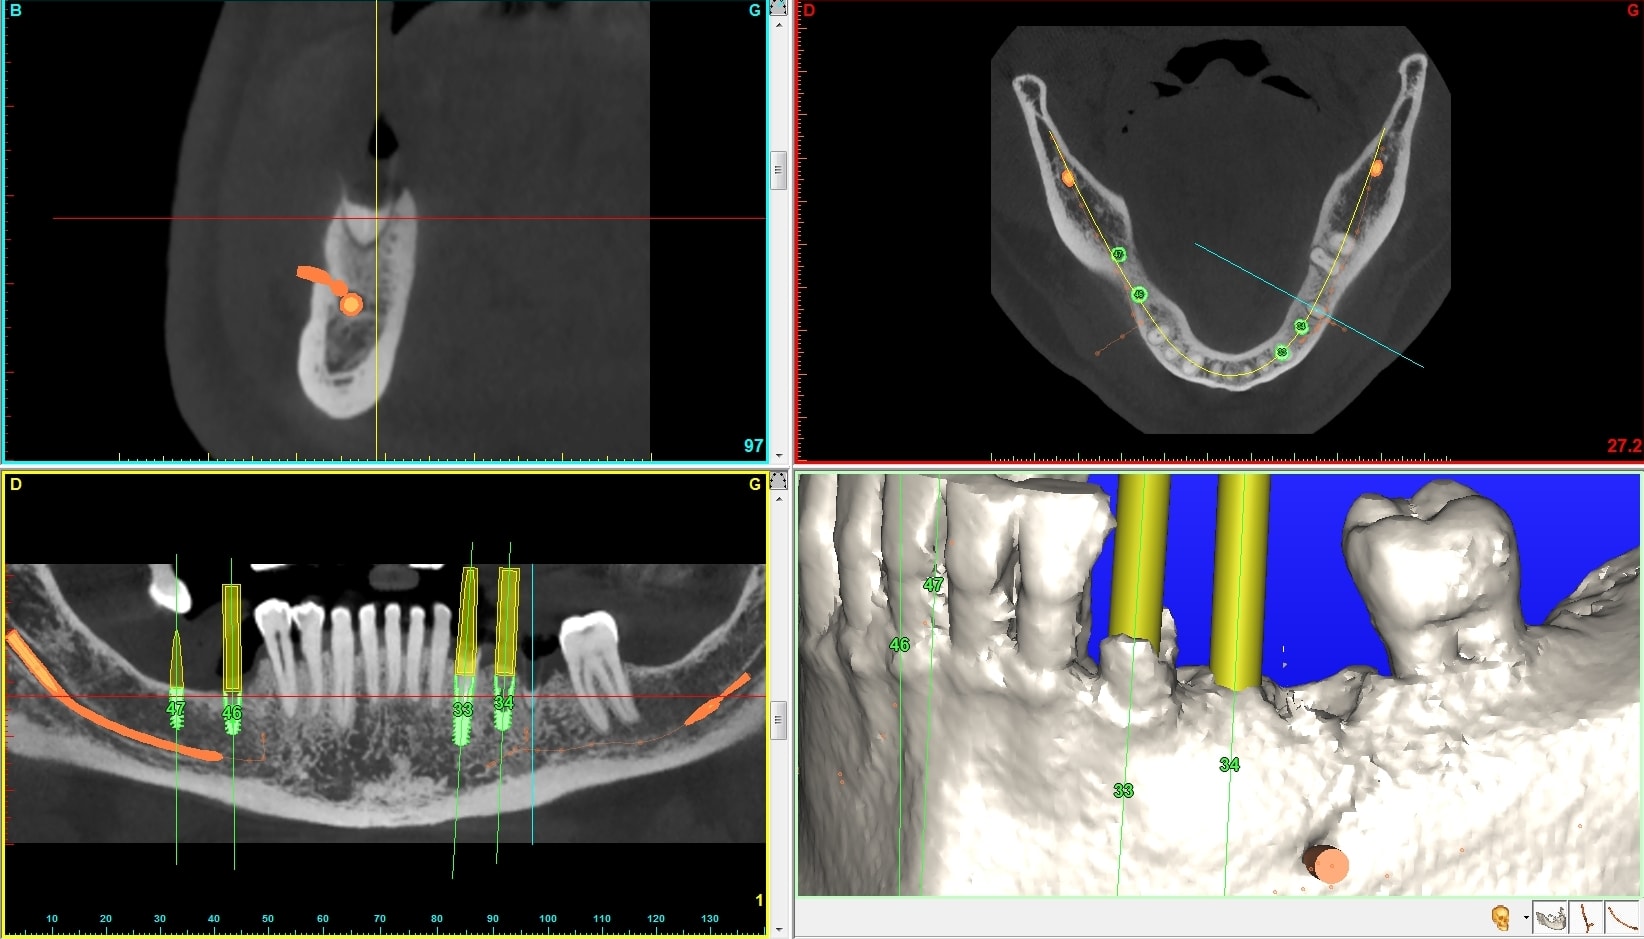

Je préfère te donner une réponse en images. Maintenant j'ai aussi essayer de faire un rapport prix / efficacité / résultat esthétique ce qui m'a amené à ce choix. Sont ils tous pertinents, bien sûr que non quelques fois (environ 200 implants /an et j'approche les 60 balais...).